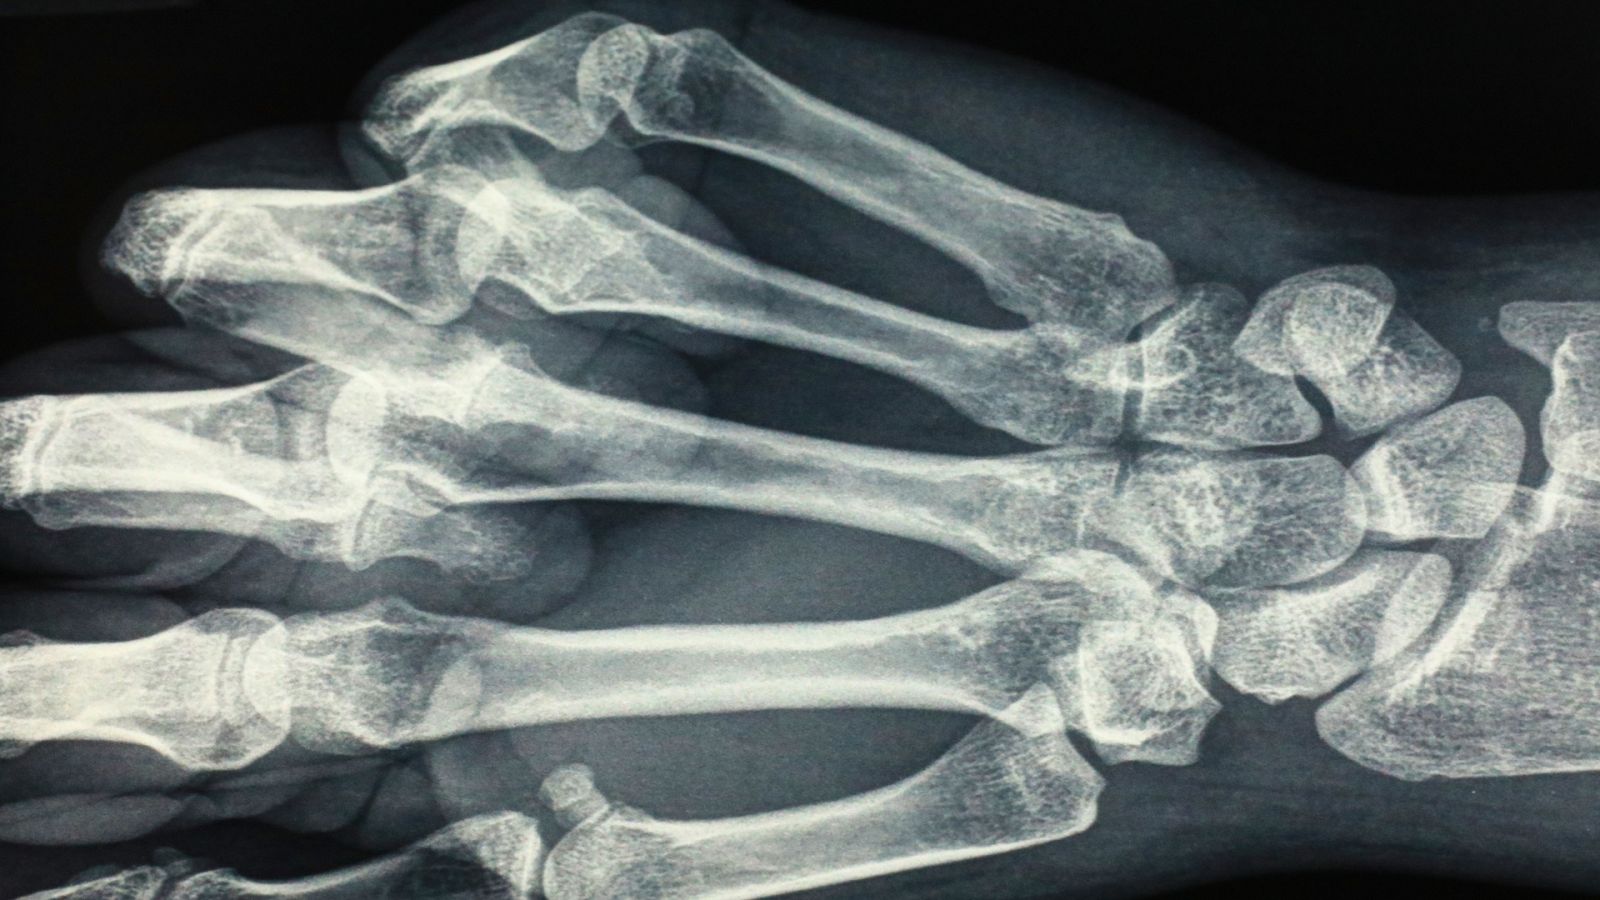

Para llegar hasta la primera máquina de rayos X portátil, primero hay que repasar los inicios de la radiología, ¿sabías que los rayos X se descubrieron por accidente? Así fue en 1895, cuando Wilhelm Conrad Röntgen experimentó con un tubo de rayos catódicos en Alemania. En ese momento, le pidió a su mujer que colocara su mano sobre una placa de metal para “fotografiarla”. De esta manera, se obtenía la primera radiografía de la historia. Este descubrimiento hizo que Röntgen fuese el primer galardonado con el Premio Nobel de Física en 1901.

¿Qué son realmente los rayos X? ¿Por qué los huesos se ven más blancos y la grasa gris?

Los rayos X son un tipo de radiación electromagnética, con más energía que la luz visible, y pueden atravesar hasta el cuerpo humano. Por lo que se refiere a los colores, estos se deben a la densidad de los tejidos, los huesos son más densos y, por tanto, absorben más rápidamente la radiación y se ven blancos. Mientras que, en tejidos menos densos como los músculos o la grasa, la radiación viaja más fácilmente, los traspasa mejor, por ello no se genera tanto contraste y se ven más grises.

Es esta densidad y el nivel de absorción que la acompaña, la razón por la que no se puede llevar metal en las radiografías, ya que el metal es muy denso y en las radiografías aparece de color blanco intenso.